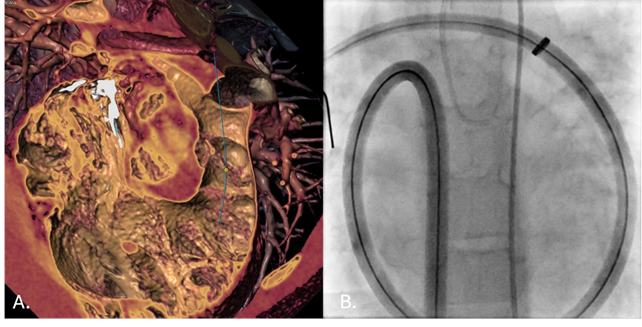

Adaptive Use of a Large-Bore Sheath to Access the Right Ventricular Outflow Tract in a Pediatric Patient

Video Supplement to "Adaptive Use of a Large-Bore Sheath to Access the Right Ventricular Outflow Tract in a Pediatric Patient" (Clinical Image).